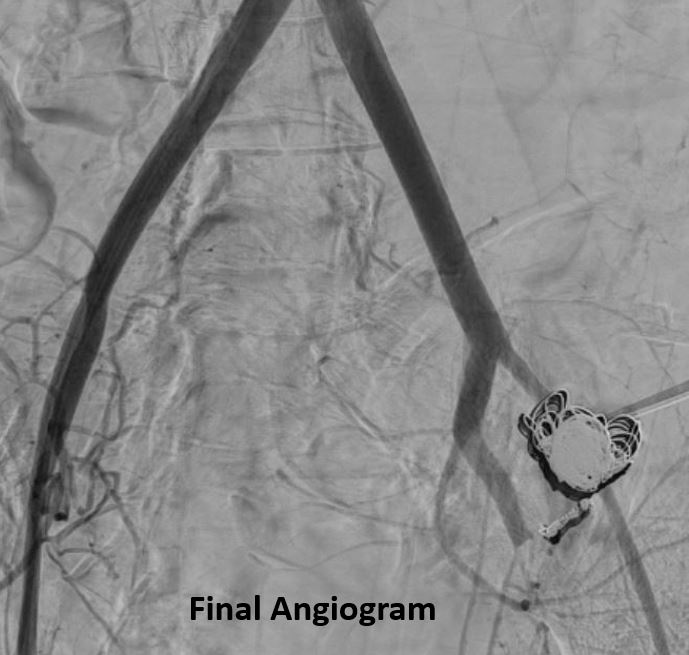

Desert rheumatism causing hemoptysis?! Elderly diabetic male with left upper lobe pulmonary coccidioidomycosis presenting with hemoptysis ~ 400 mL. Mycotic aneurysm s/p microcoil embo. Jack Hannallah MD MBA MPH Gregory J. Woodhead Shamar Young MD Society of Interventional Radiology #desertrheumatism #valleyfever #IRAD

Elderly diabetic male with left upper lobe pulmonary coccidioidomycosis presenting with hemoptysis ~ 400 mL. Mycotic aneurysm s/p microcoil embo. <a href="/HannallahMD/">Jack Hannallah MD MBA MPH</a> <a href="/woodhead/">Gregory J. Woodhead</a> <a href="/shamaryoungmd/">Shamar Young MD</a>  <a href="/SIRspecialists/">Society of Interventional Radiology</a>